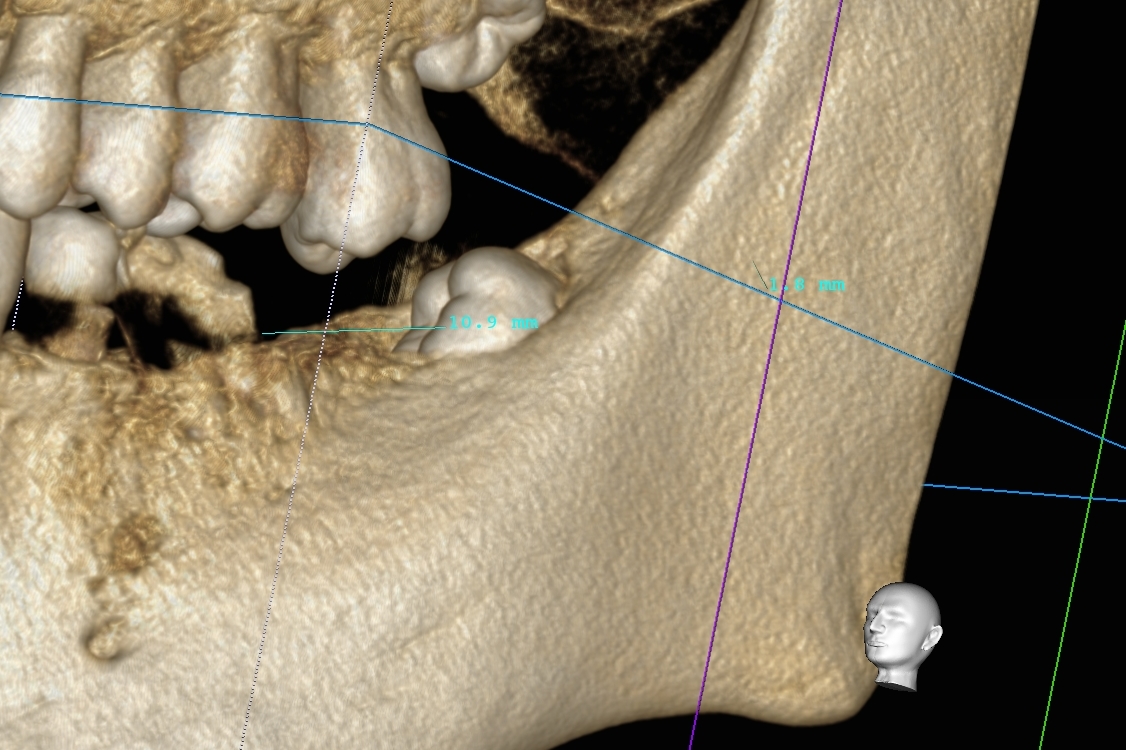

本日もインプラント手術行いました。

画面向かって右下のインプラントです!

手術時間30分、術中痛みもなく終了しております。

当院では、院長が多数のインプラント経験を有しており、このように短時間で術後も痛みが少なくなるよう最小限の歯茎しか切開を行いません。この工夫を凝らすことで、術後の痛みや腫脹を最小限にすることができます!